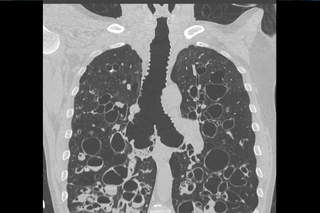

Na świecie opisano tylko około 300 przypadków choroby. Dotyczy ona młodych dorosłych, częściej występuje u mężczyzn. Charakteryzuje się osłabieniem lub zanikiem włókien elastycznych prowadzącym do patologicznego poszerzenia pierścieni chrzęstnych tchawicy oraz oskrzeli głównych. Rozpoznanie takie stawiane jest jeśli wymiar czołowy i strzałkowy średnicy tchawicy mierzony w badaniu tomografii komputerowej wynosi odpowiednio 25mm i 27mm u mężczyzn i 21mm i 23mm u kobiet.

Upośledzony klirens rzęskowy oraz zapadające się podczas oddychania główne drogi oddechowe prowadzą do nawracających infekcji z towarzyszącą znaczną ilością zalegającej ropnej wydzieliny. Leczenie pozostaje objawowe i skupia się przede wszystkim na leczeniu infekcji oraz poprawie klirensu śluzowo-rzęskowego. W pojedynczych przypadkach stosowano stentowanie zapadającej się tchawicy.